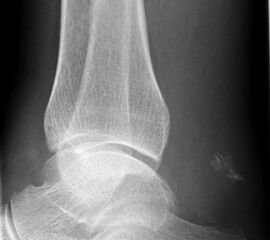

Knöcherne Ausrisse lassen sich in der seitlichen Röntgenaufnahme des Sprunggelenkes ausschließen oder beweisen (Abb. 5). Eine Sonderform bilden hier die Entenschnabelfrakturen des Kalkaneus.

Abbildung 5

Der geübte Untersucher kann anhand des seitlichen Röntgenbildes die Diagnose einer Achillessehnenruptur stellen. Die Konturen des Kager-Dreiecks – gebildet von der ventralen Begrenzung der Achillessehne, der posterioren Tibiakante und der kranialen Kalkaneuskortikalis – verstreichen im Rupturfall (Kager 1939). Die MRT- Diagnostik spielt für die Primärdiagnostik der frischen Achillessehnenruptur eine untergeordnete Rolle und ist im Normalfall nicht notwendig. Anders verhält es sich bei den chronischen Rupturen. Hier ist die MRT ein wichtiges Diagnostikum insbesondere in Hinblick auf die Beurteilung der Sehnen- und Muskeldegeneration (Abb. 6).